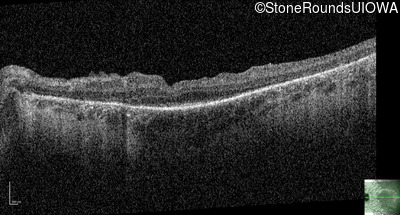

Optical Coherence Tomography - Left - 20/40

Exemplar / OCT Stack